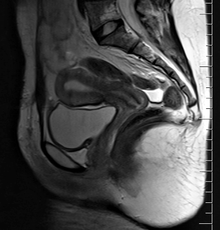

The female reproductive system (or female genital system) is made up of the internal and external sex organs that function in human reproduction. The female reproductive system is immature at birth and develops to maturity at puberty to be able to produce gametes, and to carry a fetus to full term. The internal sex organs are the uterus and Fallopian tubes, and the ovaries. The uterus or womb accommodates the embryo which develops into the fetus. The uterus also produces vaginal and uterine secretions which help the transit of sperm to the Fallopian tubes. The ovaries produce the ova (egg cells). The external sex organs are also known as the genitals and these are the organs of the vulva including the labia, clitoris and vaginal opening. The vagina is connected to the uterus at the cervix.[1]

The female internal reproductive organs are the vagina, uterus, Fallopian tubes, and ovaries.